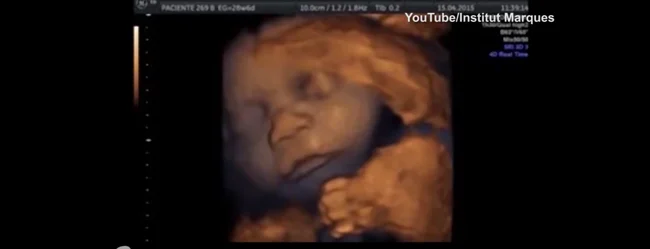

2. Чудо-дитина

У 1989 році народилася здорова дитина після того, як її мати перенесла інсульт і була визнана мертвою через загибель мозку. Він пробув у утробі жінки, підключеної до системи життєзабезпечення, 107 днів.